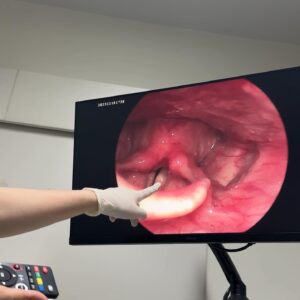

Most liked photo of Danupha Khanatheerakul with over 456.9K likes is the following photo

456.9K Likes – Danupha Khanatheerakul Instagram

Caption : สวัสดีค้าบ ส่งท้ายปีเก่าด้วยการ เป็นซีสต์ที่เส้นเสียง เย้ อ่าว ไม่ใช่ แฮะๆ หลังจากที่ใช้เสียงอยากต่อเนื่องไม่พักผ่อนนั้น มินก็เกิดอาหารคอแดงคอบวม (ซึ่งเป็นปกตินะฮะ เราพักผ่อนน้อยเองด้วย) เลยตัดสินใจไปตรวจที่โรงพยาบาลเฉพาะทาง และพบว่าตัวเป็น ซีสต์ที่เส้นเสียงข้างซ้ายข้างเดียว คือจะตัดออกก็ได้หรือจะปล่อยไว้ให้มันแตกเอง แต่มันก็อาจจะไม่แตกเองก็ได้ nobody knows คับ ถ้าผ่า โทนเสียงก็อาจจะเปลี่ยน แต่จริงๆคุณหมอบอกว่าไอ้ซีสต์นี้นวยก็น่าจะมีมาได้สักพักใหญ่ๆแล้วเนื่องจากโทนเสียงของนวยเปลี่ยนไปแล้วรอบนึง คือทุ้มต่ำลง ใช้เวลาตัดสินใจไป1สัปดาห์ ว่าจะผ่าตัดเอามันออก คือขึ้นชื่อว่าซีสต์ ตรงที่เส้นเสียงมันไม่ใช่ที่ที่มันควรอยู่อยู่แล้วอ่ะเนอะ ความจึ้งเกินอยู่ที่ว่า ก่อนหมอจะรมยาสลบ หนูสลบก่อนแล้ว กูหลับเบิ๊ดด หมอต้องปลุกมาดมยาสลบ55555 เลิศต่อมาคือ พอหมอสอดกล้องจะผ่าเอาอีก้อนออก ปรากฎว่า มัน already แตก แบบห๊ะ แบบร่างกายมัน heal ตัวเองไปแล้ว ซึ่งเป็นเรื่องดีนะคะ55555 เท่ากับว่าเราจะหายไวขึ้น ใช้เวลาพักฟื้นน้อยลง คุณหมอว่า โอกาสที่ซีสต์จะเองนี่ไม่ง่ายเลย แต่ก็ดีแล้วค่ะ หลังจากนั้นคือห้ามพูด สามวัน แต่ว่าอยากเล่าเรื่องราวให้พี่ๆฟังเลยส่งไปแบบคลิปสุดท้าย 5555555 สุดท้ายนี้ใครๆก็เป็นซีสต์ได้ รักษาเนื้อรักษาตัวไว้ด้วยนะคะทุกท่าน ปีนี้คงไม่ได้เจอกันในคอนแล้ว แต่อาจจะได้เจอมิลลิตามวัดหรือสถานที่สนุกๆนะคะ อิอิ เบิ้บบูทุกคนมากๆ ปีหน้าเจอกันใหม่ เสียงใสอย่างกับนกไนติงเกลค่ะ เสมอมาเสมอไป 🫶🏽✨Likes : 456898

456.9K Likes – Danupha Khanatheerakul Instagram

Caption : สวัสดีค้าบ ส่งท้ายปีเก่าด้วยการ เป็นซีสต์ที่เส้นเสียง เย้ อ่าว ไม่ใช่ แฮะๆ หลังจากที่ใช้เสียงอยากต่อเนื่องไม่พักผ่อนนั้น มินก็เกิดอาหารคอแดงคอบวม (ซึ่งเป็นปกตินะฮะ เราพักผ่อนน้อยเองด้วย) เลยตัดสินใจไปตรวจที่โรงพยาบาลเฉพาะทาง และพบว่าตัวเป็น ซีสต์ที่เส้นเสียงข้างซ้ายข้างเดียว คือจะตัดออกก็ได้หรือจะปล่อยไว้ให้มันแตกเอง แต่มันก็อาจจะไม่แตกเองก็ได้ nobody knows คับ ถ้าผ่า โทนเสียงก็อาจจะเปลี่ยน แต่จริงๆคุณหมอบอกว่าไอ้ซีสต์นี้นวยก็น่าจะมีมาได้สักพักใหญ่ๆแล้วเนื่องจากโทนเสียงของนวยเปลี่ยนไปแล้วรอบนึง คือทุ้มต่ำลง ใช้เวลาตัดสินใจไป1สัปดาห์ ว่าจะผ่าตัดเอามันออก คือขึ้นชื่อว่าซีสต์ ตรงที่เส้นเสียงมันไม่ใช่ที่ที่มันควรอยู่อยู่แล้วอ่ะเนอะ ความจึ้งเกินอยู่ที่ว่า ก่อนหมอจะรมยาสลบ หนูสลบก่อนแล้ว กูหลับเบิ๊ดด หมอต้องปลุกมาดมยาสลบ55555 เลิศต่อมาคือ พอหมอสอดกล้องจะผ่าเอาอีก้อนออก ปรากฎว่า มัน already แตก แบบห๊ะ แบบร่างกายมัน heal ตัวเองไปแล้ว ซึ่งเป็นเรื่องดีนะคะ55555 เท่ากับว่าเราจะหายไวขึ้น ใช้เวลาพักฟื้นน้อยลง คุณหมอว่า โอกาสที่ซีสต์จะเองนี่ไม่ง่ายเลย แต่ก็ดีแล้วค่ะ หลังจากนั้นคือห้ามพูด สามวัน แต่ว่าอยากเล่าเรื่องราวให้พี่ๆฟังเลยส่งไปแบบคลิปสุดท้าย 5555555 สุดท้ายนี้ใครๆก็เป็นซีสต์ได้ รักษาเนื้อรักษาตัวไว้ด้วยนะคะทุกท่าน ปีนี้คงไม่ได้เจอกันในคอนแล้ว แต่อาจจะได้เจอมิลลิตามวัดหรือสถานที่สนุกๆนะคะ อิอิ เบิ้บบูทุกคนมากๆ ปีหน้าเจอกันใหม่ เสียงใสอย่างกับนกไนติงเกลค่ะ เสมอมาเสมอไป 🫶🏽✨Likes : 456898

456.9K Likes – Danupha Khanatheerakul Instagram

Caption : สวัสดีค้าบ ส่งท้ายปีเก่าด้วยการ เป็นซีสต์ที่เส้นเสียง เย้ อ่าว ไม่ใช่ แฮะๆ หลังจากที่ใช้เสียงอยากต่อเนื่องไม่พักผ่อนนั้น มินก็เกิดอาหารคอแดงคอบวม (ซึ่งเป็นปกตินะฮะ เราพักผ่อนน้อยเองด้วย) เลยตัดสินใจไปตรวจที่โรงพยาบาลเฉพาะทาง และพบว่าตัวเป็น ซีสต์ที่เส้นเสียงข้างซ้ายข้างเดียว คือจะตัดออกก็ได้หรือจะปล่อยไว้ให้มันแตกเอง แต่มันก็อาจจะไม่แตกเองก็ได้ nobody knows คับ ถ้าผ่า โทนเสียงก็อาจจะเปลี่ยน แต่จริงๆคุณหมอบอกว่าไอ้ซีสต์นี้นวยก็น่าจะมีมาได้สักพักใหญ่ๆแล้วเนื่องจากโทนเสียงของนวยเปลี่ยนไปแล้วรอบนึง คือทุ้มต่ำลง ใช้เวลาตัดสินใจไป1สัปดาห์ ว่าจะผ่าตัดเอามันออก คือขึ้นชื่อว่าซีสต์ ตรงที่เส้นเสียงมันไม่ใช่ที่ที่มันควรอยู่อยู่แล้วอ่ะเนอะ ความจึ้งเกินอยู่ที่ว่า ก่อนหมอจะรมยาสลบ หนูสลบก่อนแล้ว กูหลับเบิ๊ดด หมอต้องปลุกมาดมยาสลบ55555 เลิศต่อมาคือ พอหมอสอดกล้องจะผ่าเอาอีก้อนออก ปรากฎว่า มัน already แตก แบบห๊ะ แบบร่างกายมัน heal ตัวเองไปแล้ว ซึ่งเป็นเรื่องดีนะคะ55555 เท่ากับว่าเราจะหายไวขึ้น ใช้เวลาพักฟื้นน้อยลง คุณหมอว่า โอกาสที่ซีสต์จะเองนี่ไม่ง่ายเลย แต่ก็ดีแล้วค่ะ หลังจากนั้นคือห้ามพูด สามวัน แต่ว่าอยากเล่าเรื่องราวให้พี่ๆฟังเลยส่งไปแบบคลิปสุดท้าย 5555555 สุดท้ายนี้ใครๆก็เป็นซีสต์ได้ รักษาเนื้อรักษาตัวไว้ด้วยนะคะทุกท่าน ปีนี้คงไม่ได้เจอกันในคอนแล้ว แต่อาจจะได้เจอมิลลิตามวัดหรือสถานที่สนุกๆนะคะ อิอิ เบิ้บบูทุกคนมากๆ ปีหน้าเจอกันใหม่ เสียงใสอย่างกับนกไนติงเกลค่ะ เสมอมาเสมอไป 🫶🏽✨Likes : 456898

456.9K Likes – Danupha Khanatheerakul Instagram

Caption : สวัสดีค้าบ ส่งท้ายปีเก่าด้วยการ เป็นซีสต์ที่เส้นเสียง เย้ อ่าว ไม่ใช่ แฮะๆ หลังจากที่ใช้เสียงอยากต่อเนื่องไม่พักผ่อนนั้น มินก็เกิดอาหารคอแดงคอบวม (ซึ่งเป็นปกตินะฮะ เราพักผ่อนน้อยเองด้วย) เลยตัดสินใจไปตรวจที่โรงพยาบาลเฉพาะทาง และพบว่าตัวเป็น ซีสต์ที่เส้นเสียงข้างซ้ายข้างเดียว คือจะตัดออกก็ได้หรือจะปล่อยไว้ให้มันแตกเอง แต่มันก็อาจจะไม่แตกเองก็ได้ nobody knows คับ ถ้าผ่า โทนเสียงก็อาจจะเปลี่ยน แต่จริงๆคุณหมอบอกว่าไอ้ซีสต์นี้นวยก็น่าจะมีมาได้สักพักใหญ่ๆแล้วเนื่องจากโทนเสียงของนวยเปลี่ยนไปแล้วรอบนึง คือทุ้มต่ำลง ใช้เวลาตัดสินใจไป1สัปดาห์ ว่าจะผ่าตัดเอามันออก คือขึ้นชื่อว่าซีสต์ ตรงที่เส้นเสียงมันไม่ใช่ที่ที่มันควรอยู่อยู่แล้วอ่ะเนอะ ความจึ้งเกินอยู่ที่ว่า ก่อนหมอจะรมยาสลบ หนูสลบก่อนแล้ว กูหลับเบิ๊ดด หมอต้องปลุกมาดมยาสลบ55555 เลิศต่อมาคือ พอหมอสอดกล้องจะผ่าเอาอีก้อนออก ปรากฎว่า มัน already แตก แบบห๊ะ แบบร่างกายมัน heal ตัวเองไปแล้ว ซึ่งเป็นเรื่องดีนะคะ55555 เท่ากับว่าเราจะหายไวขึ้น ใช้เวลาพักฟื้นน้อยลง คุณหมอว่า โอกาสที่ซีสต์จะเองนี่ไม่ง่ายเลย แต่ก็ดีแล้วค่ะ หลังจากนั้นคือห้ามพูด สามวัน แต่ว่าอยากเล่าเรื่องราวให้พี่ๆฟังเลยส่งไปแบบคลิปสุดท้าย 5555555 สุดท้ายนี้ใครๆก็เป็นซีสต์ได้ รักษาเนื้อรักษาตัวไว้ด้วยนะคะทุกท่าน ปีนี้คงไม่ได้เจอกันในคอนแล้ว แต่อาจจะได้เจอมิลลิตามวัดหรือสถานที่สนุกๆนะคะ อิอิ เบิ้บบูทุกคนมากๆ ปีหน้าเจอกันใหม่ เสียงใสอย่างกับนกไนติงเกลค่ะ เสมอมาเสมอไป 🫶🏽✨Likes : 456898